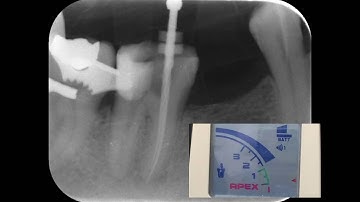

Working length determination by EAL